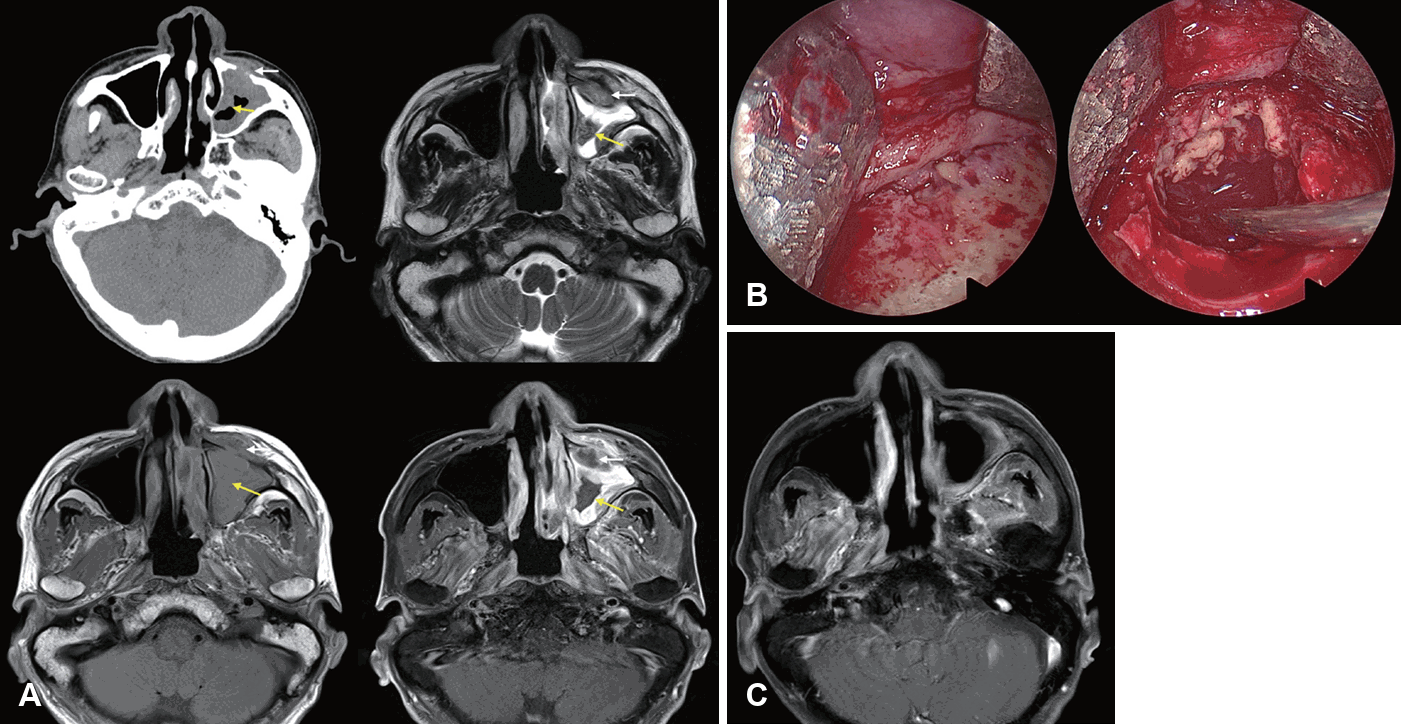

Gadolinium-enhanced MRI (Gd-MRI) has emerged as a superior modality for evaluating IFRS. The “black turbinate sign” of sinonasal tissue lacking contrast enhancement on MRI was first described to correspond to devitalized mucosa from angioinvasive hyphae [54]. However, it should be noted that nonenhancing portions of the turbinate are observed in 30% of patients without IFRS, especially in the posterior portion of inferior turbinates. Non-enhancing turbinates in immunocompetent patients retain peripheral (likely normal) mucosa enhancement and thin septa, which are key features distinguishing pathologic black turbinates from infiltrative nonenhancing lesions (IFRS), which exhibit infiltrative non-enhancement extending to adjacent structures without a smooth, thin enhancing margin [55]. MRI had a higher sensitivity than CT for diagnosing AIFRS with similar specificity, PPV, NPV, and accuracy, and LoCE on MRI showed 76.5% agreement with endoscopic mucosal findings. Therefore, MRI is more sensitive than CT in detecting early changes of AIFRS and is an appropriate initial diagnostic method when AIFRS is suspected, given suspicious endoscopic findings [52]. In 2017, the American College of Radiology Appropriateness Criteria recommended that an MRI of the face and sinuses, including orbit and brain, is the study of choice for evaluating patients with suspected IFRS. CT may be a valuable complement to MRI for surgical planning [56].

Furthermore, Lagos, et al. [41] reported that LoCE (75% sensitivity, 84% specificity, 50% PPV, and 94% NPV), extrasinonasal extension (60% sensitivity, 89% specificity, 60% PPV, and 89% NPV), and orbit compromise (50% sensitivity, 95% specificity, 75% PPV, and 86% NPV) on MRI were significantly associated with AIFRS. Kim, et al. [13] highlighted the significance of the loss of contrast enhancement (LoCE) on MRI as a characteristic finding of AIFRS. LoCE reflects tissue ischemia secondary to angiocentric invasion by fungal organisms. MRI is particularly valuable for the early detection of AIFRS, evaluation of extrasinonasal extension, assessment of intracranial and intraorbital involvement, distinguishing between viable and necrotic tissues, guiding the extent of surgical debridement, and monitoring treatment response (Fig. 2) [13]. Furthermore, LoCE at the skull base was reported as an independent poor prognostic factor (hazard ratio [HR]= 35.846, p=0.004) in patients with extrasinonasal IFRS, possibly because extensive necrotic lesions at the skull base cannot be removed entirely. A rather extensive resection may lead to serious morbidity, such as internal carotid artery injury, untreated cerebrospinal fluid leakage, meningitis, or brain damage [14].

Gadolinium (Gd)-enhanced MR images and intraoperative finding of a patient with acute invasive fungal sinusitis. A: Loss of contrast enhancement (LoCE) was preoperatively identified in the right maxillary sinus and retroantral area (arrow). B: Necrotic tissue in the posterior wall of the maxillary sinus and retroantral area was completely resected via endoscopic medial maxillectomy approach. C: Postoperative Gd-enhanced MR image showed no remnant LoCE lesions, and the patient was successfully treated with surgical debridement and antifungal therapy.